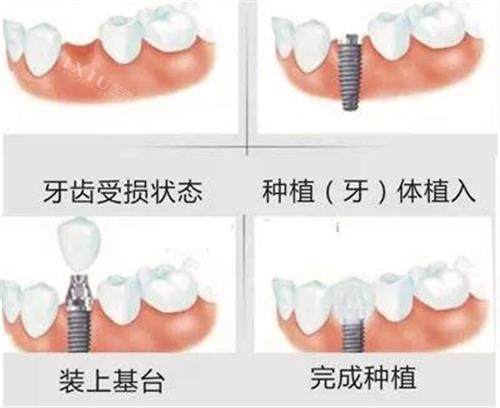

刚走进医院,导诊人员就热情迎接,耐心询问情况后,快速安排王大爷进行口腔检查。检查过程中,医护人员动作轻柔,还不断安抚王大爷紧张的情绪。随后,种植科医生根据王大爷的口腔 CT 影像、牙槽骨条件等,为他量身定制了种植牙方案,并详细讲解了手术原理和术后修复情况。

手术当天,王大爷虽然有些忐忑,但医生熟练的操作和手术室温馨的氛围,让他渐渐放松下来。整个种植手术比预期时间更短,创口小、出血少,术后仅有轻微不适感。经过几个月的改善,王大爷的新牙稳固又好用,他高兴地说:“仪美口腔的医生技术真不错!现在我能正常吃饭了,感觉身体都变好了。这里的医护人员特别负责,每次复查都很仔细,强烈推荐给有需要的人!”